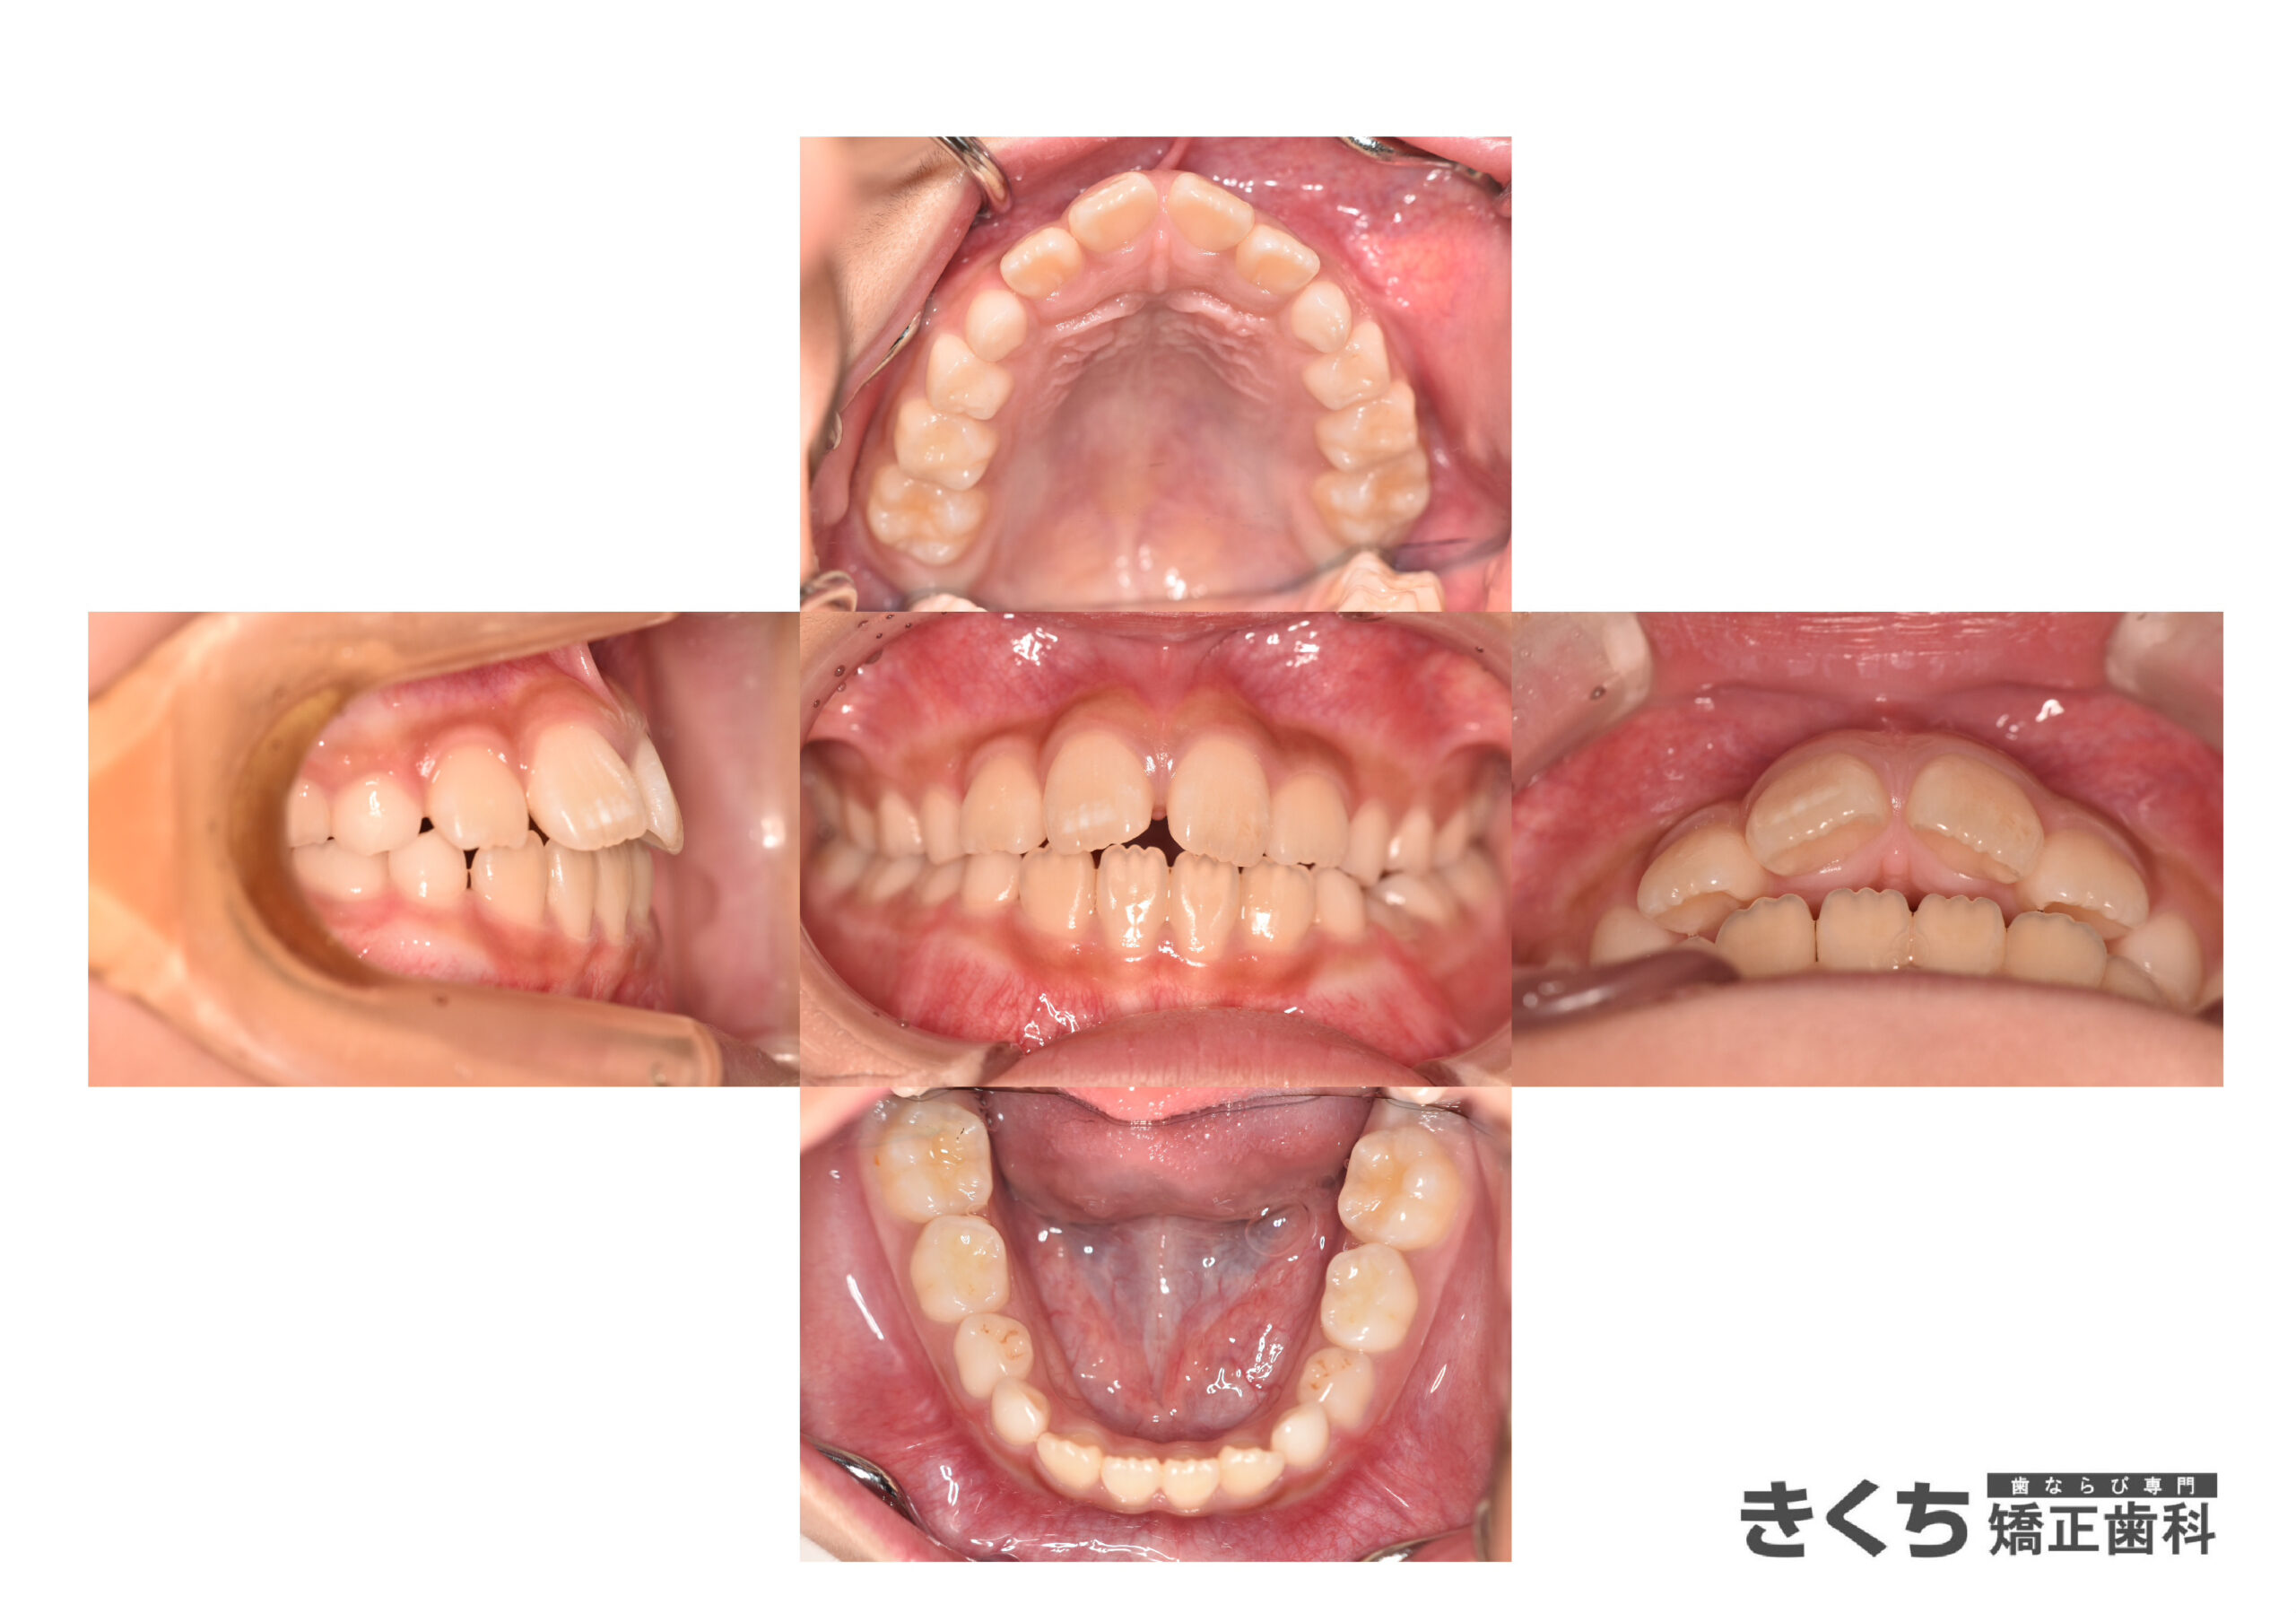

初診時7歳、かみ合わせを気にして来院

学校検診や他院にて今すぐ矯正治療を始めたほうがいいと指摘を受けた

→6ヶ月ごとのペースで経過観察

口腔筋機能を改善するために指導を行いました。

↓↓↓↓↓↓↓ 6ヶ月後

口腔筋機能 の改善だけで、気にしていたかみ合わせが自然に改善しました。